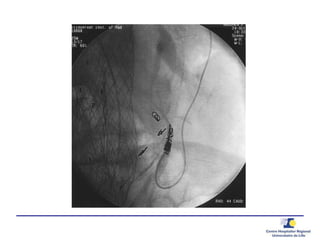

Ponction translombaire –

embolisation directe

Ponction

Anévrysmographie

Guide de pression 0.014’’

20 G needle0.014’’ PressureWire

 Pression

Aorta

Sac